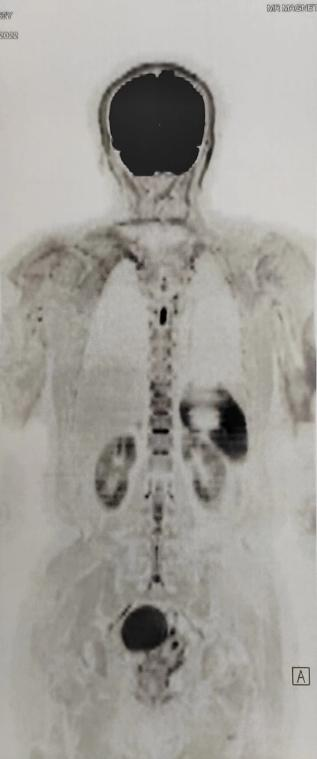

Lumina 3T智能磁体具备业内最大成像范围55cm,能够得到完整大范围静态和动态高清成像

Lumina 3T同时具备业内大孔径,70cm的检查孔径,能够为患者提供更宽敞和舒适的检查环境,适应危重、肥胖、幽闭综合症患者检查,减少受检过程中压抑、沉闷等不良感受。

Siemens Lumina 3.0T磁共振的引进,又为我院临床、教学再添一项利器,当应用压缩感知技术完成一个膝关节的常规序列和体位时,可较常规扫描节约30%的时间,多种软件的配合可提高诊断质量,为患者带来更加舒适、便捷、高效的诊断服务。

目前,新引进的3.0T磁共振与我院现有的Siemens Area 1.5T高配置磁共振相配合,可全面覆盖我院各临床科室的所有检查患者预约时间和等候检查时间明显缩短,从而改善患者就医体验,科室做到只要患者符合检查条件即可在就诊当日完成检查。3.0T磁共振引进必将有力地带动我院乃至河西地区医疗技术的快速发展,为广大人民群众的健康保驾护航。